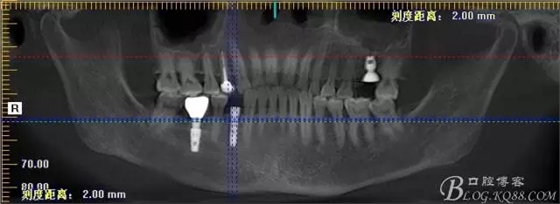

那么看下術(shù)前CBCT吧

上圖為術(shù)前CBCT情況,26號(hào)牙顯示頰根和腭根間有一比較大的區(qū)域骨頭吸收,對(duì)于即刻種植還是有難度的,植入深度需要適當(dāng)加深,那么也許使用BICON 種植體相對(duì)更加合適

上圖44號(hào)牙位做即刻種植毫無難度可言,我們要做的只是患者術(shù)后反應(yīng)更小,植入方向更好而已

術(shù)后片顯示植入情況都可以